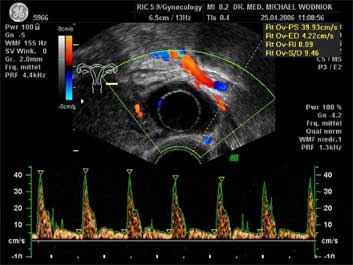

Ultraschall des kleinen Beckens mit der Vaginalsonde Die Ultraschalluntersuchung ist ein bildgebendes Verfahren, welches die Reflektion oder Echos von Ultraschallwellen in den unterschiedlichen Geweben und Organen ausnützt um computergestützt Schnittbilder aus dem Inneren des Körpers zu erstellen. Durch moderne hochleistungsfähige Mikroprozessoren ist es in den letzten Jahren möglich geworden, auch 3-dimensionale oder sogar bewegte 3-dimensionale (4-D) Bilder bzw. Bildsequenzen zu erzeugen. Beides können wir Ihnen in der Praxis anbieten. Eine Ultraschalluntersuchung ist ungefährlich und schmerzfrei. Durch die Anwendung von Dopplerverfahren, mit welchen wir den Blutfluss in den Organen feststellen und messen können, erweitern wir die Untersuchung um die funktionelle Dimension. Ein weiterer Bestandteil unseres Leistungsspektrums ist die farbkodierte Dopplersonographie. Farbkodiert sind entweder die Richtung des Blutflusses oder dessen Intensität. Über die computergestütze Berechnung des Blutflusswiderstandes ist im Einzelnen eine Aussage bzw. Vorhersage über die qualitative und quantitative Durchblutung möglich. (Plazentadurchblutung, kindliche Blutgefässe, Durchblutungsmuster bei verschiedenen Tumoren des Unterleibes und der Brustdrüsen) Ultraschalluntersuchungen haben in unserem Fachgebiet vielfältige Anwendungsmöglichkeiten gefunden. Besonders faszinierend ist der Einsatz im Bereich der vorgeburtlichen Diagnostik. Bereits in der 10. Schwangerschaftswoche ist es möglich, die Extremitäten des Embryos darzustellen und Aussagen zum Körperumrissbild zu machen (Ausschluss von Spaltbildungen, Nackentransparenzmessung). Auch im Bereich der Gynäkologie ist die Bedeutung des Ultraschalls stetig gewachsen und hat sich als erweiterte Vorsorge etabliert. Durch die vaginale Ultraschalluntersuchung können bereits kleine Veränderungen entdeckt werden, die sich der manuellen Tastuntersuchung noch entziehen. Auffällige Tastbefunde an den Eierstöcken sind durch den Einsatz von 3D / 4D in Kombination mit der Farbdoppleruntersuchung besser interpretierbar und können dadurch Frauen unnötige abklärende Operation ersparen. Die Anwendung des 3D Ultraschall, insbesondere im Coronarschnitt, lässt eine effektive Beurteilung für Veränderungen (Polypen, Karzinome) der Gebärmutterschleimhaut zu. ![]() ![]() ![]() ![]() ![]() |